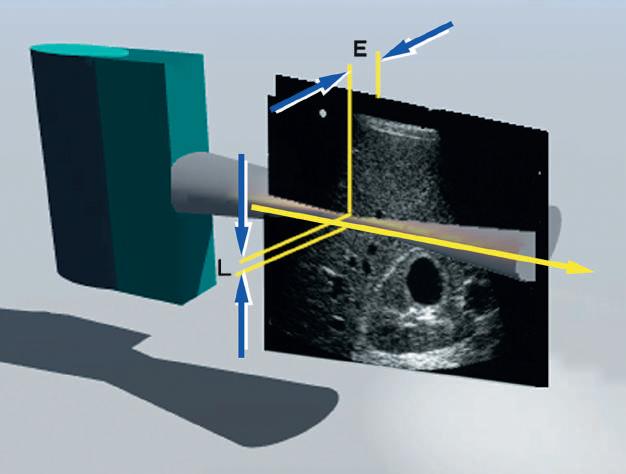

FIG. 1.26 Lateral and Elevation Resolution. Resolution in the planes perpendicular to the beam axis is an important determinant of image quality. Lateral resolution (L) is resolution in the plane perpendicular to the beam and parallel to the transducer and is determined by the width of the ultrasound beam. Lateral resolution is controlled by focusing the beam, usually by electronic phasing to alter the beam width at a selected depth of interest. Azimuth or elevation resolution (E) is determined by the slice thickness in the plane perpendicular to the beam and the transducer. Elevation resolution is controlled by the construction of the transducer. Both lateral resolution and elevation resolution are less than the axial resolution.

In addition to axial resolution, resolution in the planes perpendicular to the beam axis must also be considered. Lateral resolution refers to resolution in the plane perpendicular to the beam and parallel to the transducer and is determined by the width of the ultrasound beam. Azimuth resolution, or elevation resolution, refers to the slice thickness in the plane perpendicular to the beam and to the transducer (Fig. 1.26). The width and thickness of the ultrasound beam are important determinants of image quality. Excessive beam width and thickness limit the ability to delineate small features and may obscure shadowing and enhancement from small structures, such as breast microcalcifications and small thyroid cysts. The width and thickness of the ultrasound beam determine lateral resolution and elevation resolution, respectively. Lateral and elevation resolutions are significantly poorer than the axial resolution of the beam. Lateral resolution is controlled by focusing the beam, usually by electronic phasing, to alter the beam width at a selected depth of interest. Elevation resolution is determined by the construction of the transducer and generally cannot be controlled by the user.